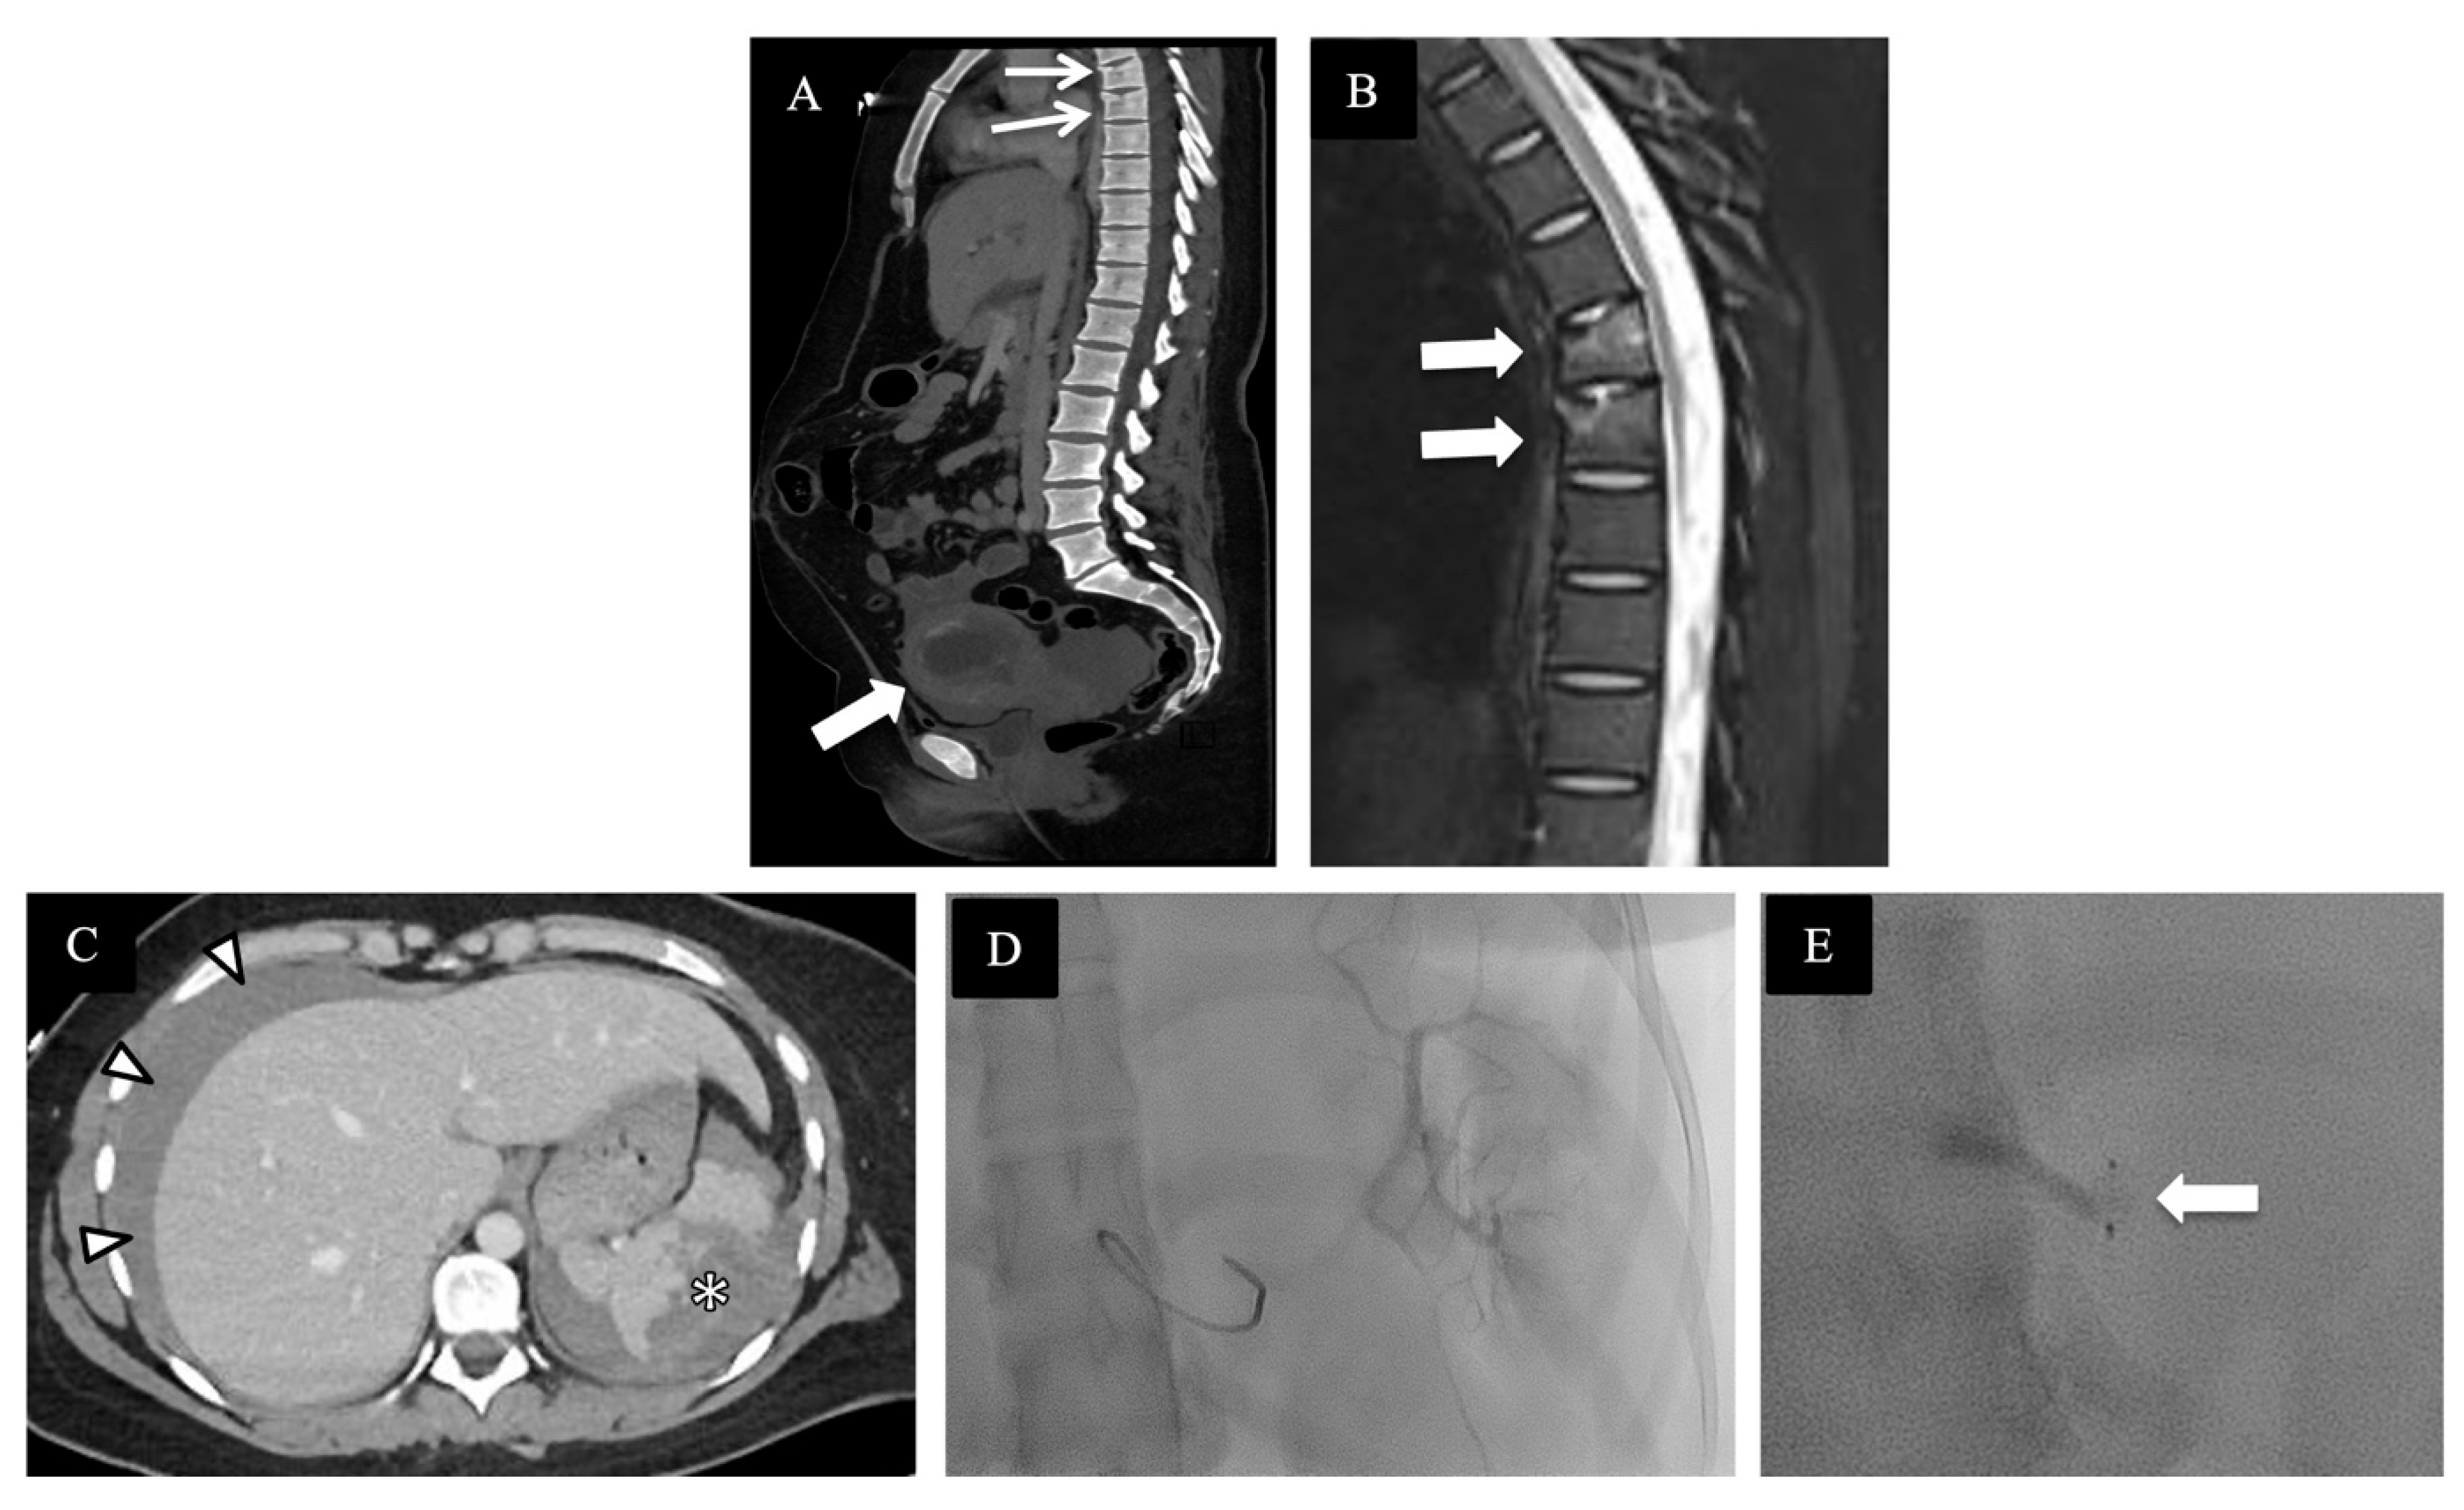

4. Review of Local Presentations